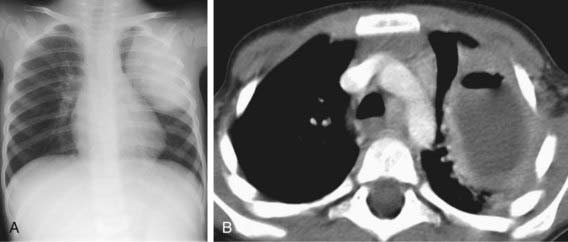

Diagnosis is most commonly made on the basis of chest radiography. Classically, the chest radiograph shows a parenchymal inflammation with a cavity containing an air-fluid level (Fig. 394-1). A chest CT scan can provide better anatomic definition of an abscess, including location and size (Fig. 394-2).

Figure 394-2 Pulmonary abscess in a 2 yr old boy with persistent cough. A, Chest radiograph shows large oval mass in the left upper lobe. B, CT scan demonstrates an abscess with a thick enhancing wall that contains both air and fluid.

(From Slovis TL, editor: Caffey’s pediatric diagnostic imaging, ed 11, Philadelphia, 2008, Mosby, p 1297.)